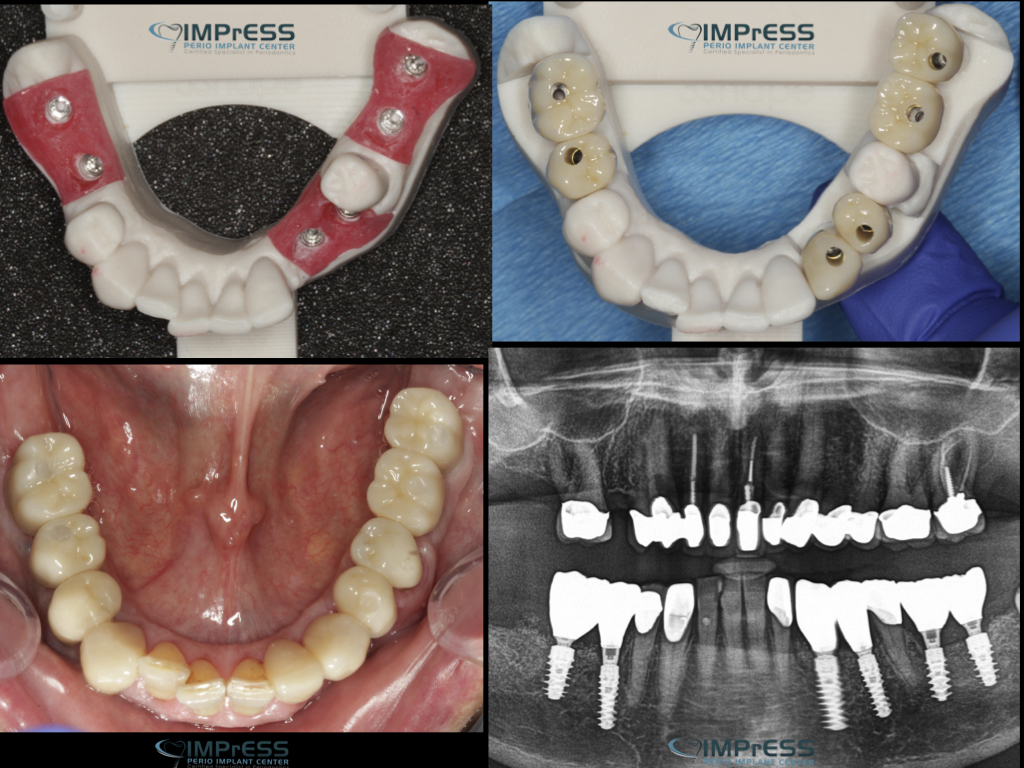

Full Mouth Reconstruction with Fixed Implant Bridge – All on X

All on X implant Full Mouth Implant Reconstruction All on 4 Implants IMPrESS Perio Implant Center Vancouver Burnaby Periodontist Prosthodontist Implant Specialist Dr. Noroozi Periodontist Implant Specialist